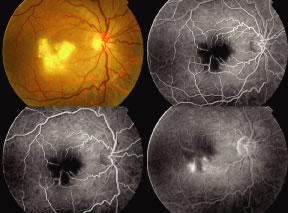

A variable number of eyes, up to 75%, develop retinal detachments (Fig. 5). Prophylactic laser for demarcating the areas of active retinitis from normal retina has been advocated to create chorioretinal adhesions that prevent retinal detachments around sites of retinal break formation (which usually occur at the zone between affected and healthy retina). Han and associates43 reported five cases treated with prophylactic laserpexy in addition to antiviral, steroid, and antiplatelet therapy. After 15 months of follow-up, no retinal detachments were noted. Sternberg and coworkers44 described a 75% decrease in the rate of retinal detachment using prophylactic photocoagulation. Some have advocated the creation of a “new ora serrata” by applying confluent rows of laser burns posterior to the areas of retinitis. However, if traction forces from vitreous organization, epiretinal membrane (ERM) formation, or proliferative vitreoretinopathy develop as they commonly do, the contractile forces will be able to overcome any increased chorioretinal adhesion created by the laserpexy. However, McDonald and associates45 reported failure of prophylactic peripheral laserpexy to prevent retinal detachment in ARN patients. In addition, many cases of ARN result in a severe vitritis, limiting the view for a planned laserpexy (Fig. 6). Therefore, vitrectomy with endolaser and concomitant encircling of the eye with a scleral buckle to reduce traction may be required in some patients.46,47 Decisions relating to the need for scleral buckling to support retinal breaks and the use of silicone oil or long-acting gases to repair retinal detachments should be made by an experienced vitreoretinal surgeon.40,48 Selection of cases to undergo operation should be made with consideration given to optic nerve function, visual potential, and medical control of retinitis.